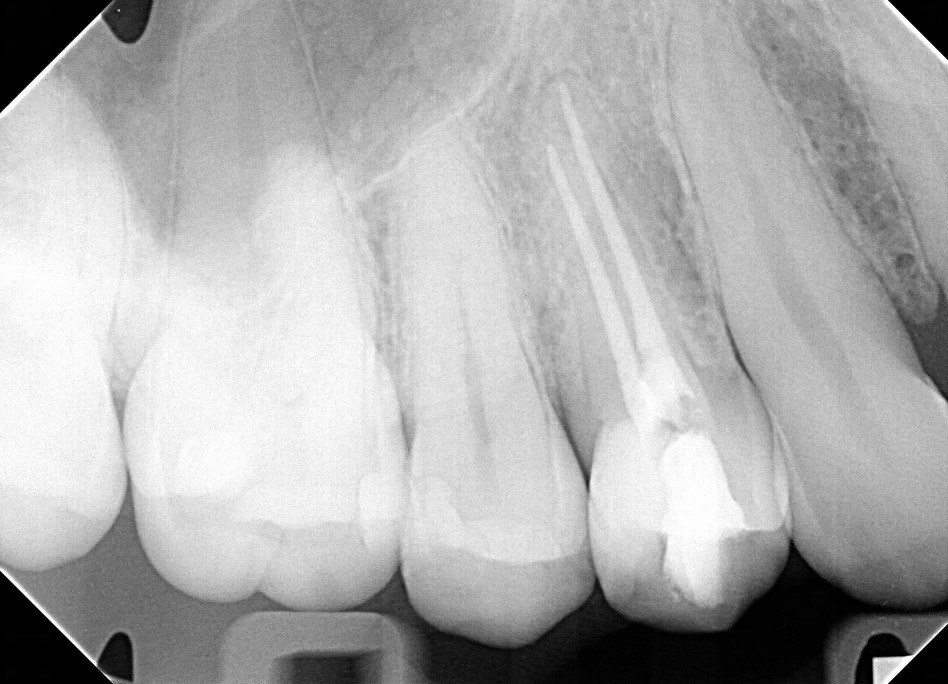

Case Study: Root Canal

Generate some text here